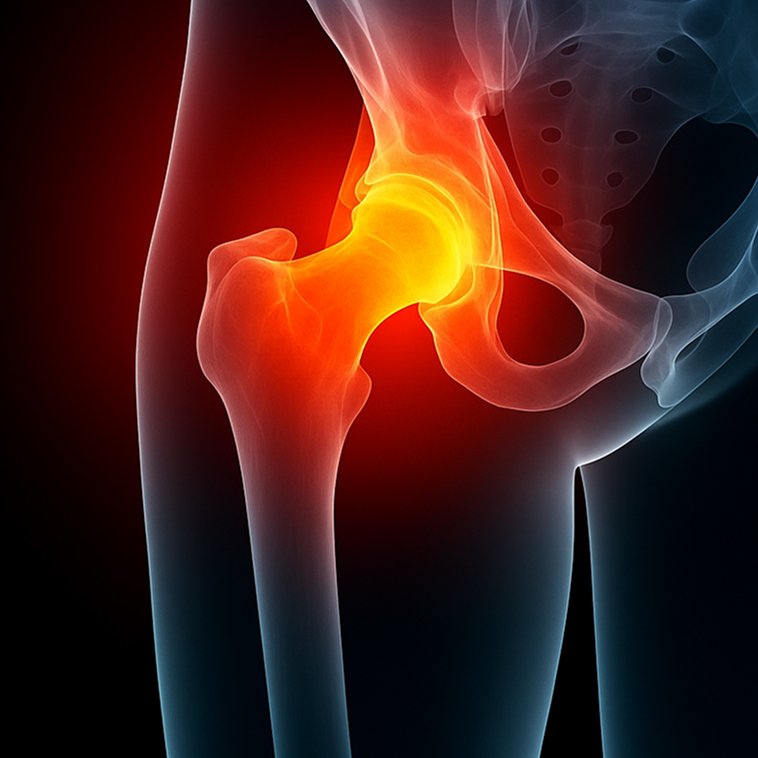

Pelvic reconstruction surgery addresses damage or instability in the pelvic region, restoring function and reducing pain for those affected by trauma, congenital abnormalities, or degenerative conditions. The pelvis supports essential movements and stability, and any disruption can severely limit daily activities. At Valiant Clinic, we understand how these issues affect your comfort and independence, and we’re dedicated to helping you regain stability and mobility with advanced pelvic reconstruction procedures.

Who is Pelvic Reconstruction recommended for?

Traumatic Pelvic Fractures

Pelvic reconstruction is essential for those with severe fractures or instability caused by accidents or injuries.

Pelvic Deformities

Individuals with congenital or acquired pelvic abnormalities can benefit from surgery to improve alignment and reduce pain.

Chronic Pelvic Pain & Instability

For those experiencing ongoing pain or instability in the pelvic region, reconstruction can restore function and support daily living.